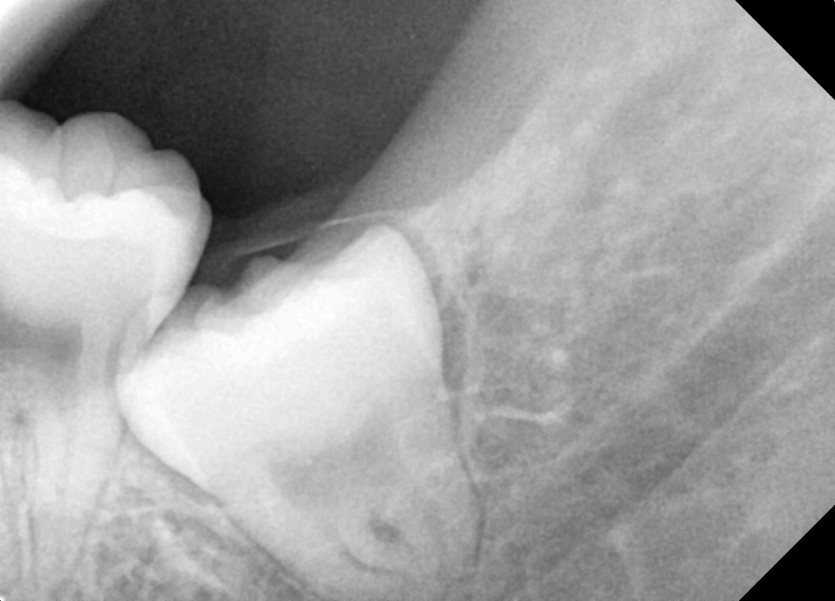

#38,48 사랑니 발치

구강 외과 전문의가 당일 발치했습니다.